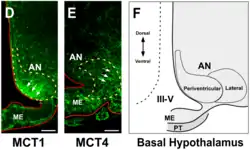

- ↑ Cortés-Campos C., Elizondo R., Llanos P., Uranga R.M., Nualart F., García M.A. (2011). «MCT Expression and Lactate Influx/Efflux in Tanycytes Involved in Glia-Neuron Metabolic Interaction». PLoS ONE 6 (1): e16411. doi:10.1371/journal.pone.0016411. Consultado el 10 de enero de 2021.